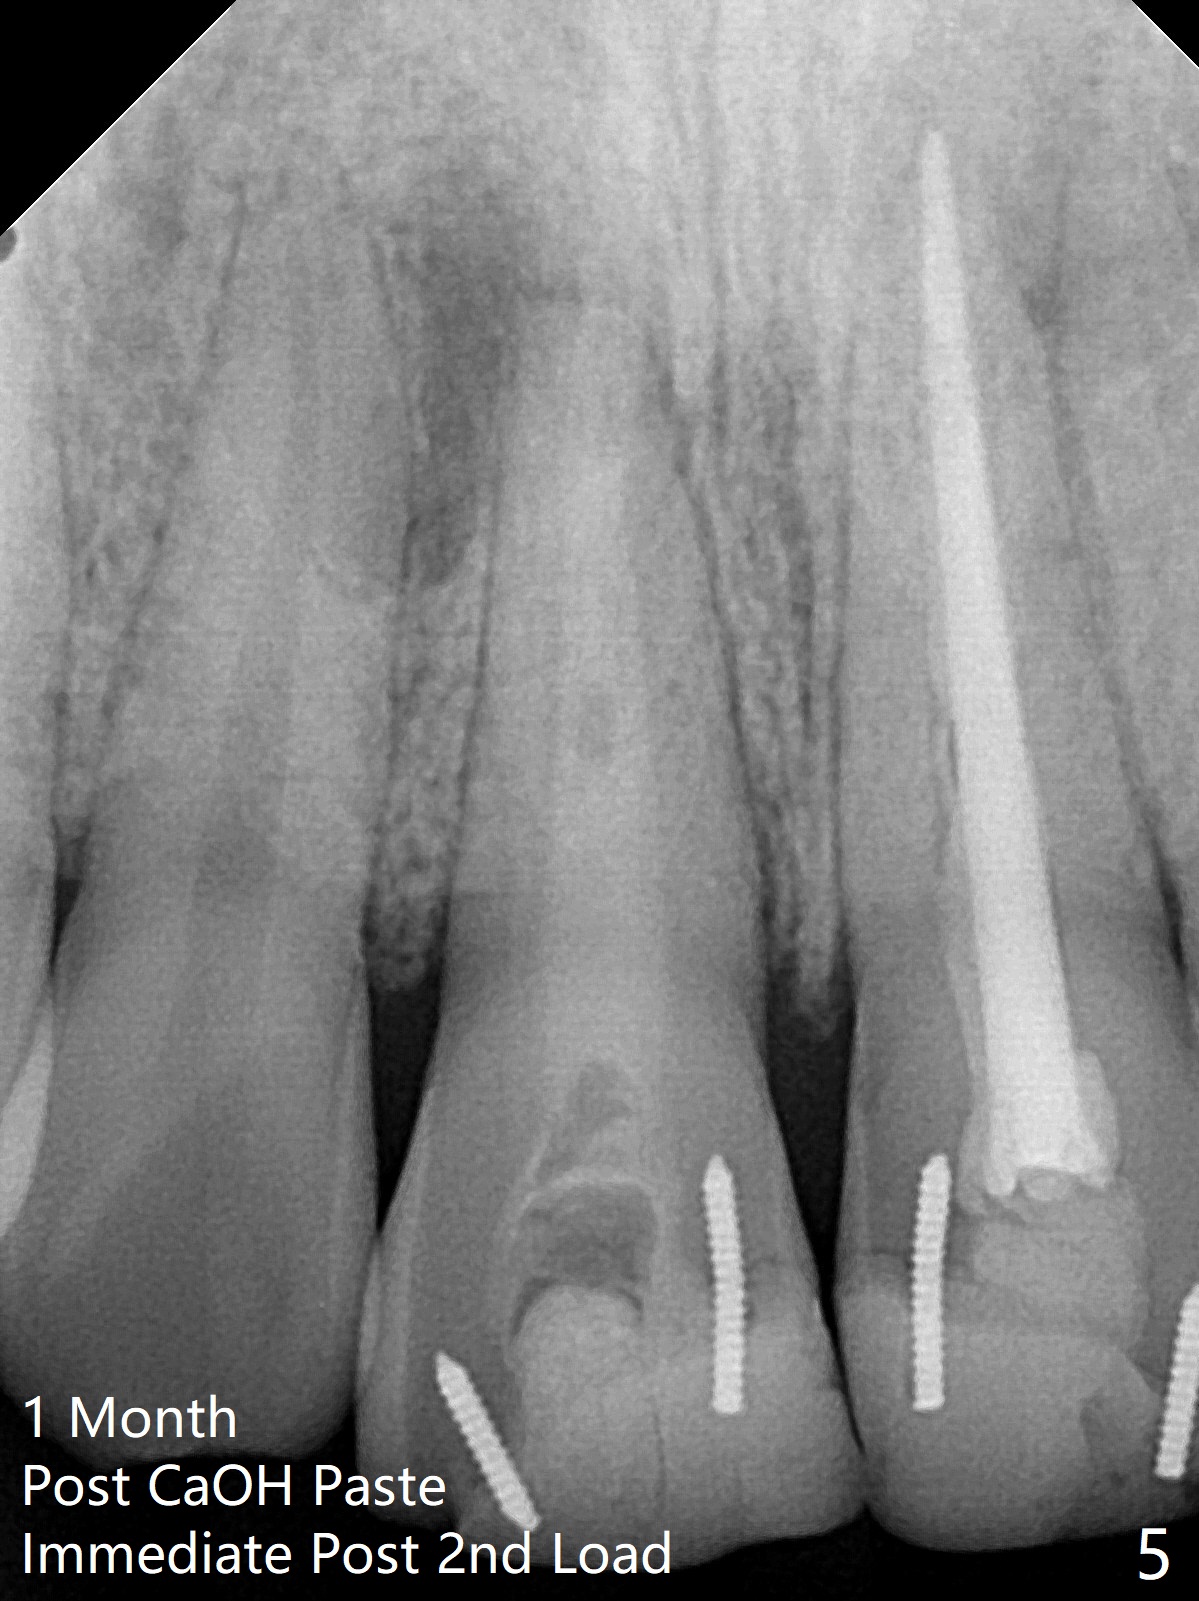

15岁男去年急诊来诊所左上1疼痛(图一:9号牙),两个中切牙8-9岁外伤,侧切牙活性测定:活髓,建议8,9 apexification。一年后(这个月)他又回来要求9号牙树脂修复(图二:*),他在马来西亚看望爸爸时,突然牙痛在那里做根管治疗。现在两个中切牙颊侧根尖都有触痛。树脂修补后,他回来做8号牙牙髓治疗,想象根管宽大,但是根尖2-3毫米根管弯曲,必须事先弯曲10号扩大针才能进入,最后扩大针是rotary file, 40/.04, 21.5毫米(图三),好像工作长度不够,仅仅增加半个毫米,使用15号扩大针,病人觉得疼痛(没用局麻药),不再扩大,保持原来根尖狭窄(可以吗?)。反复冲洗后放置氢氧化钙糊剂(图四),根管仿佛挺粗的,根尖根管还需要扩大吗?根尖片清晰度不好,看不出根尖闭锁与否,需要拍摄CT吗?需要使用MTA促进根尖关闭吗?